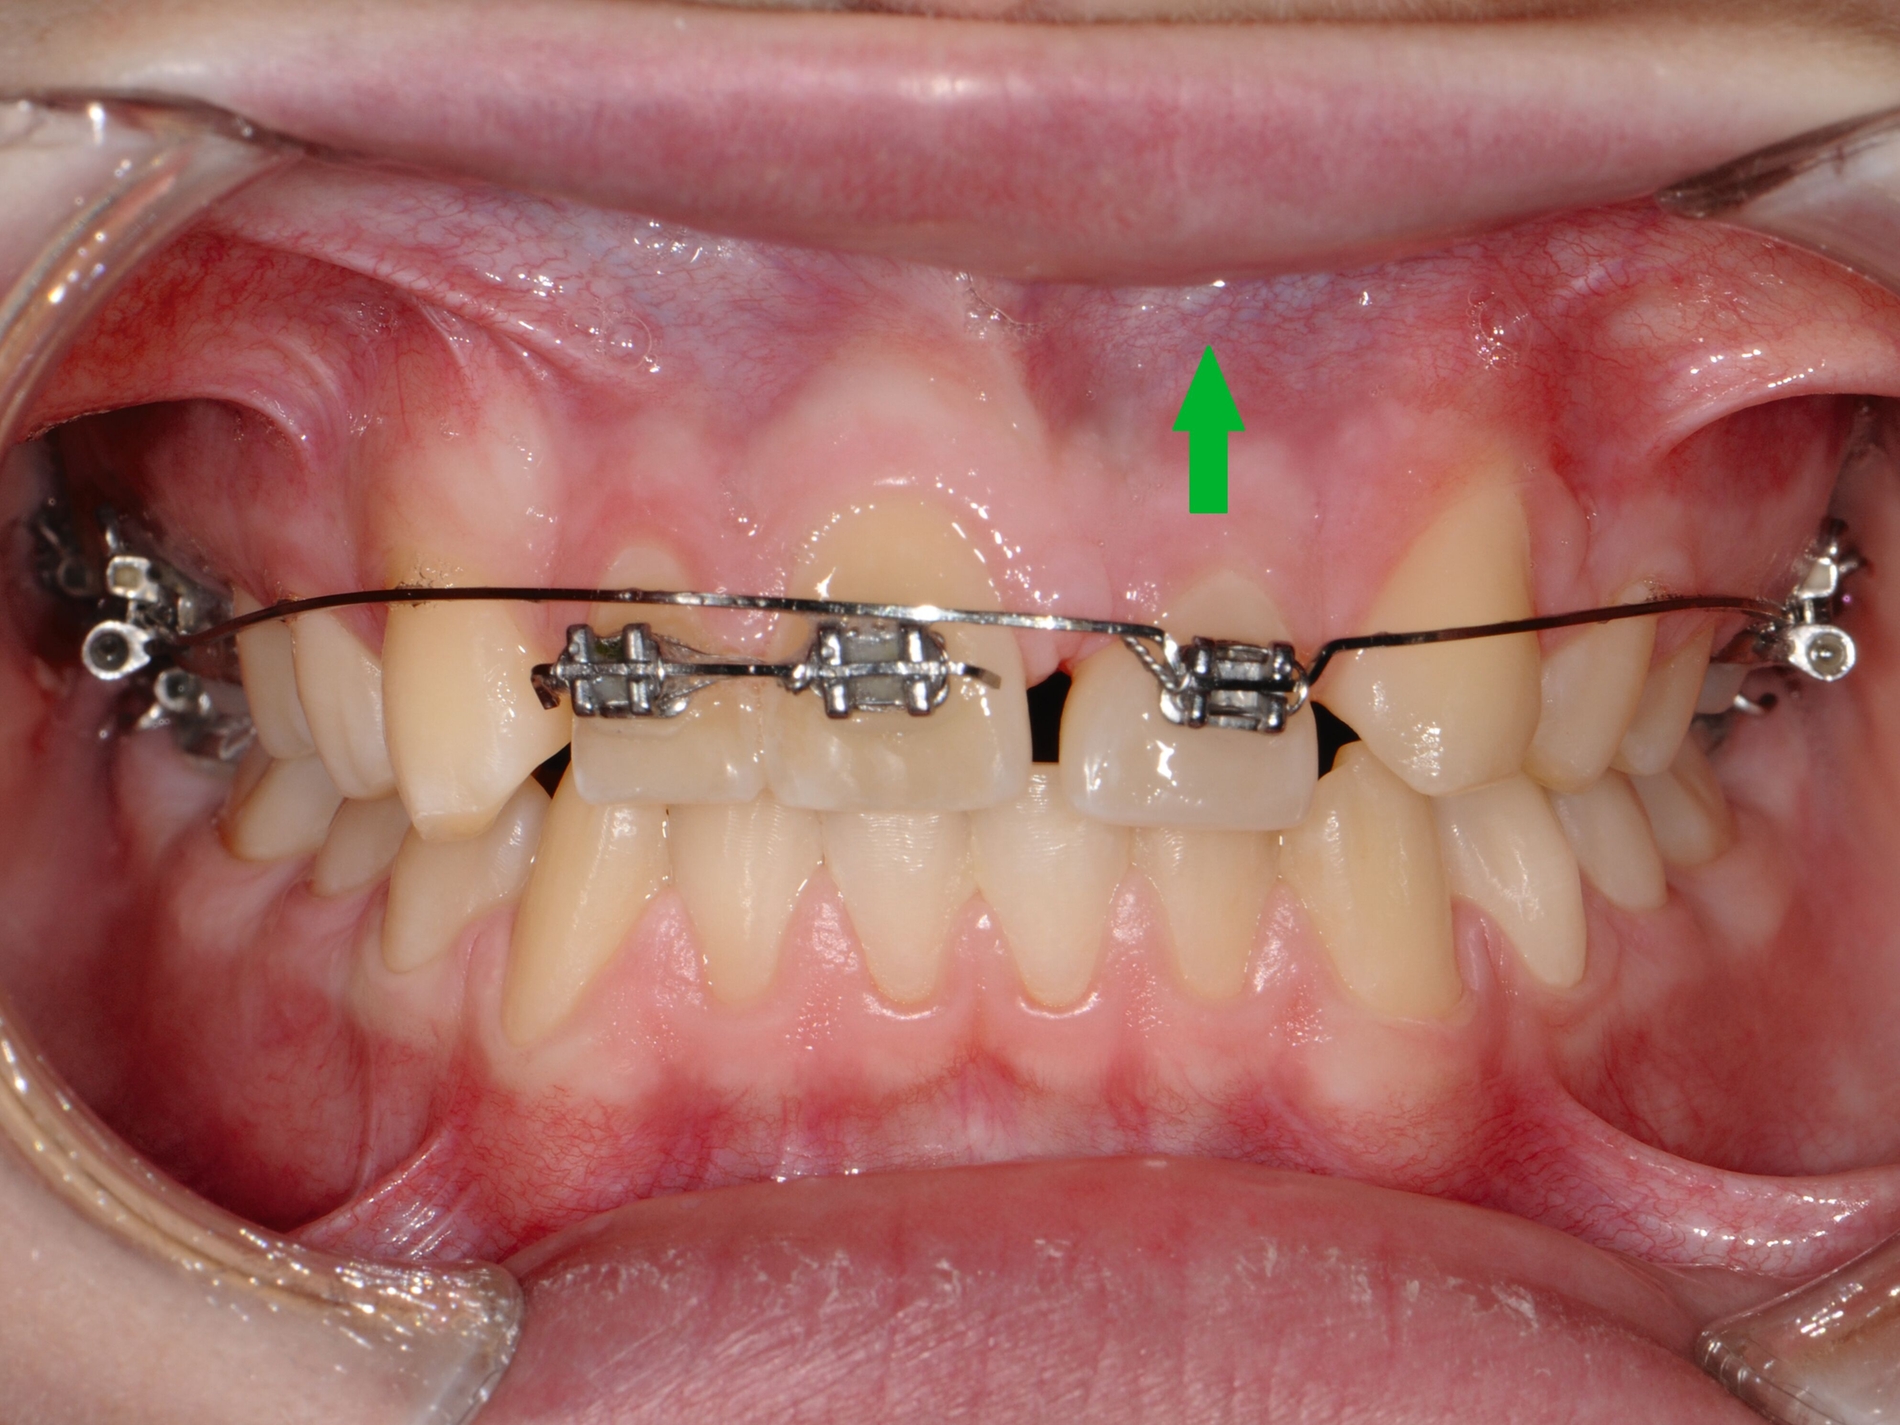

Gerade Patienten mit einer stark vergrößerten Frontzahnstufe und einer fehlenden Lippenbedeckung der Schneidezähne können von einer frühzeitigen kieferorthopädischen Korrektur vor der zweiten Wechselgebissphase profitieren [Bauss et al., 2008]. Malokklusionen erhöhen das Risiko für traumatische Zahnverletzungen [Bauss et al., 2008; Corrêa-Faria et al., 2016; O'Mullane, 1973]. Eine kieferorthopädische Behandlung für Kinder mit solchen Merkmalen (Abbildung 1) könnte daher hilfreich sein, um Frontzahntraumata sowie die daraus resultierenden Spätfolgen zu verhindern.

Eine kontinuierlich aktualisierte Serie von Cochrane-Reviews [Thiruvenkatachari et al., 2015; Thiruvenkatachari et al., 2013] zur Behandlung von Klasse-II-Malokklusionen bestätigt aktuell [Batista et al., 2018] den Vorteil einer frühen (zweiphasigen) Behandlung bei der Reduktion der Inzidenz von Schneidezahntraumata.